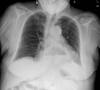

Neumonía basal.